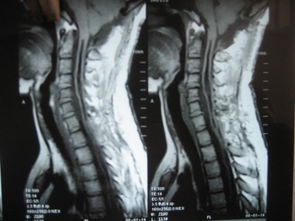

脊髓空洞癥就是脊髓的一種慢性、進(jìn)行性的病變。病因不十分清楚,其病變特點(diǎn)是脊髓內(nèi)形成管狀空腔以及膠質(zhì)增生。常好發(fā)于頸部脊髓。當(dāng)病變累及延髓時(shí),則稱為延髓空洞癥。那么脊髓空洞有哪些癥狀呢?